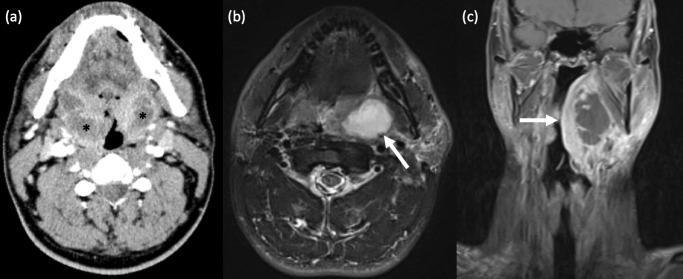

咽病理学的影像学表现。

Imaging of pharyngeal pathology.

The pharynx plays a significant role in swallowing and speech, and this is reflected in both its complex anatomy and degree of physiological motility. Patients who present with pharynx-related symptoms such as sore throat, globus, dysphagia or dysphonia will usually undergo visual and nasal endoscopic examination in the first instance. Imaging is frequently required to supplement clinical assessment and this typically involves MRI and CT. However, fluoroscopy, ultrasound and radionuclide imaging are valuable in certain clinical situations. The aforementioned complexity of the pharynx and the myriad of pathologies which may arise within it often make radiological evaluation challenging. In this pictorial review, we aim to provide a brief overview of cross-sectional pharyngeal anatomy and present the radiological features of a variety of pharyngeal pathologies, both benign and malignant.

咽在吞咽和言语中起着重要作用,这反映在其复杂的解剖结构和生理运动程度上。出现咽痛、咽部异物感、吞咽困难或发音困难等咽部相关症状的患者通常首先进行视诊和鼻内镜检查。影像学检查常需要补充临床评估,通常包括 MRI 和 CT。然而,透视、超声和放射性核素成像在某些临床情况下具有重要价值。上述咽的复杂性和可能发生的多种病理改变常常使影像学评估具有挑战性。在本影像学综述中,我们旨在简要概述咽的横断解剖结构,并介绍各种良性和恶性咽病变的影像学特征。